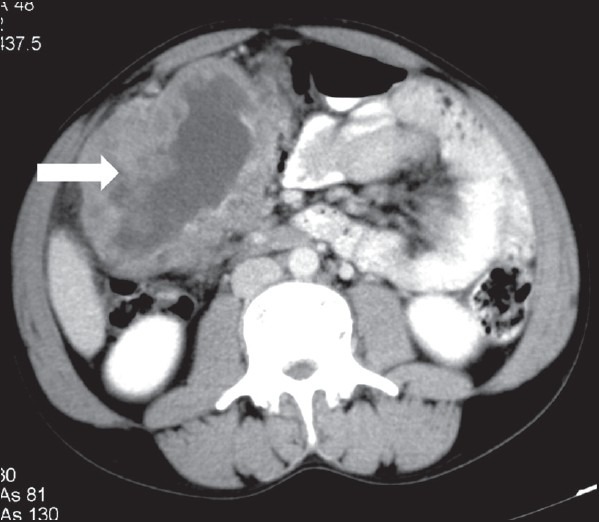

| Figure 2:Ileal gastrointestinal stromal tumor in a 45-year-old male — axial contrast-enhanced computed tomography image showing heterogeneously enhancing exophytic mass lesion (black arrowhead) arising from ileal loop causing mild aneurysmal dilatation (white arrowhead)

| Figure 2:Ileal gastrointestinal stromal tumor in a 45-year-old male — axial contrast-enhanced computed tomography image showing heterogeneously enhancing exophytic mass lesion (black arrowhead) arising from ileal loop causing mild aneurysmal dilatation (white arrowhead)